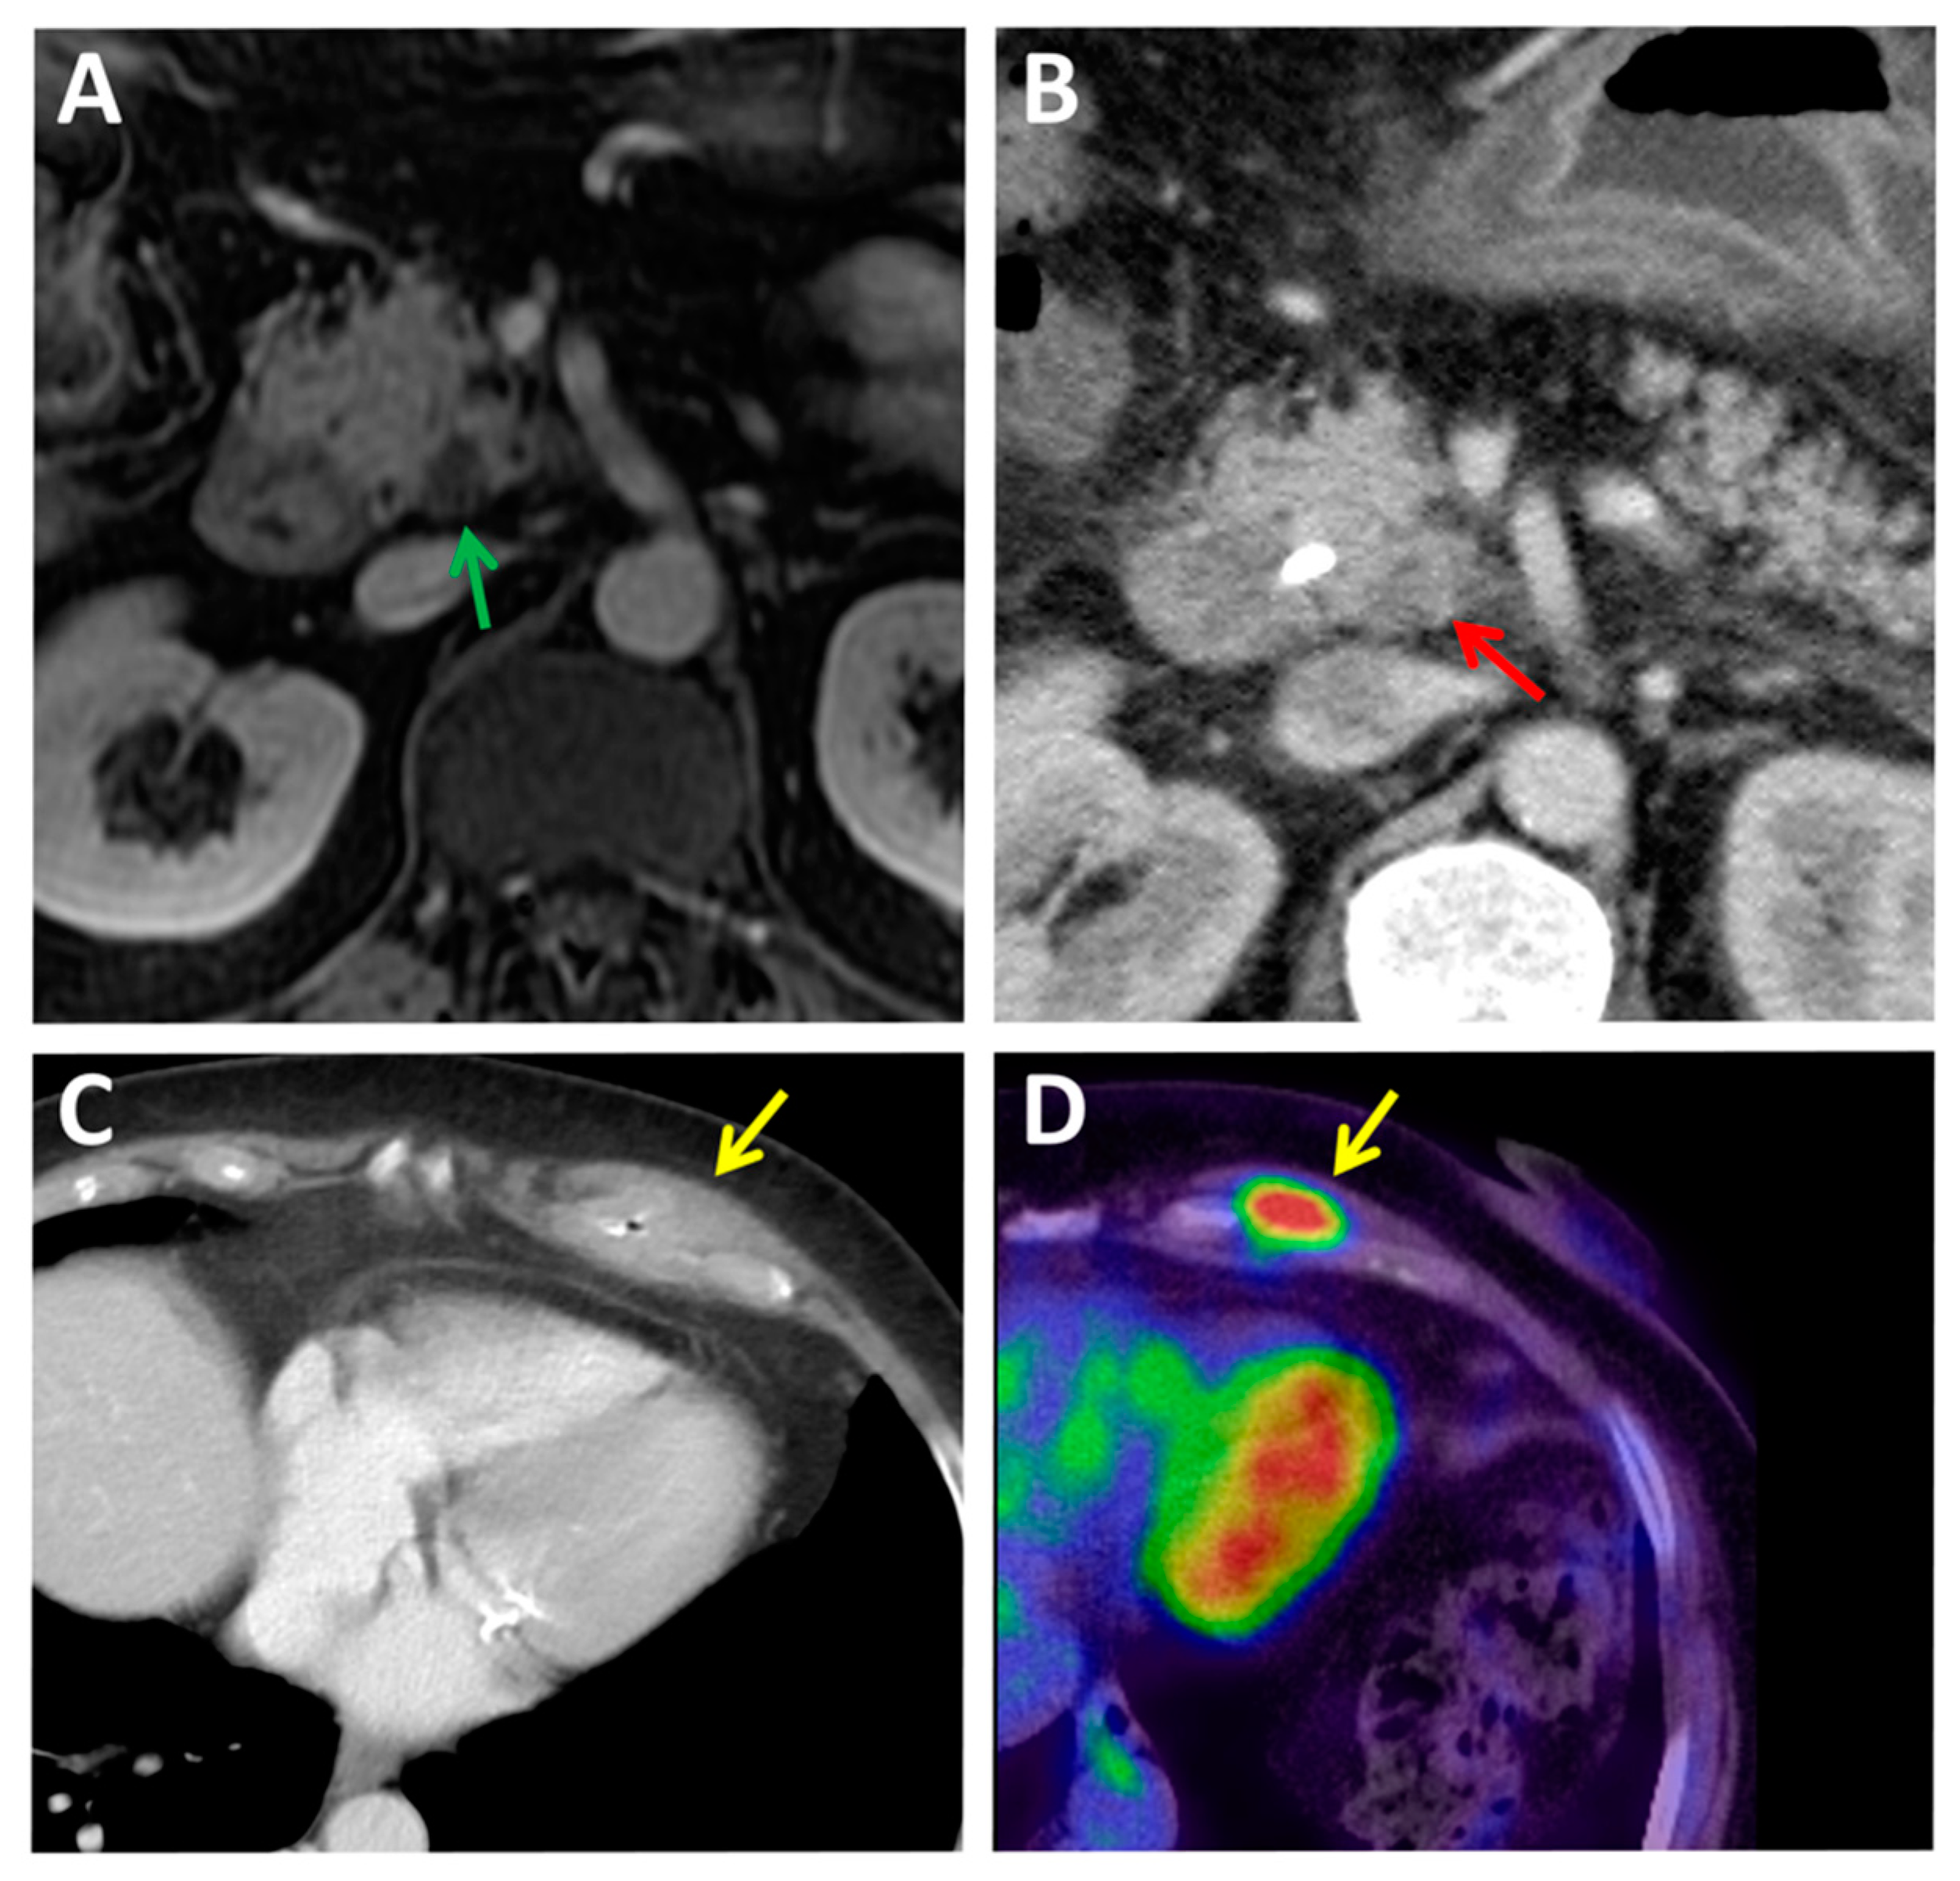

2.1. Computed Tomography

2.4. PET Hybrid Imaging